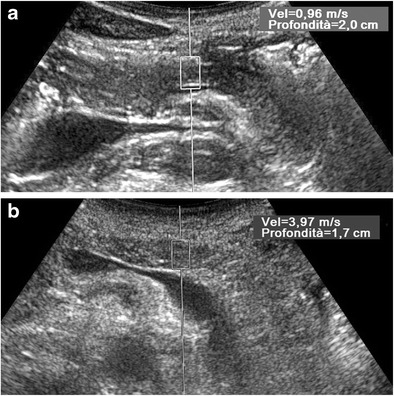

Fig. 13.

ARFI evaluation of the pancreas. Axial US scans with ROI placed in the pancreatic body. The SWV value is much lower (0.96 vs. 3.97 m/s) in a healthy 38-year-old man (a) than in a 48-year-old man (b) with severe chronic alcoholic non-obstructive pancreatitis